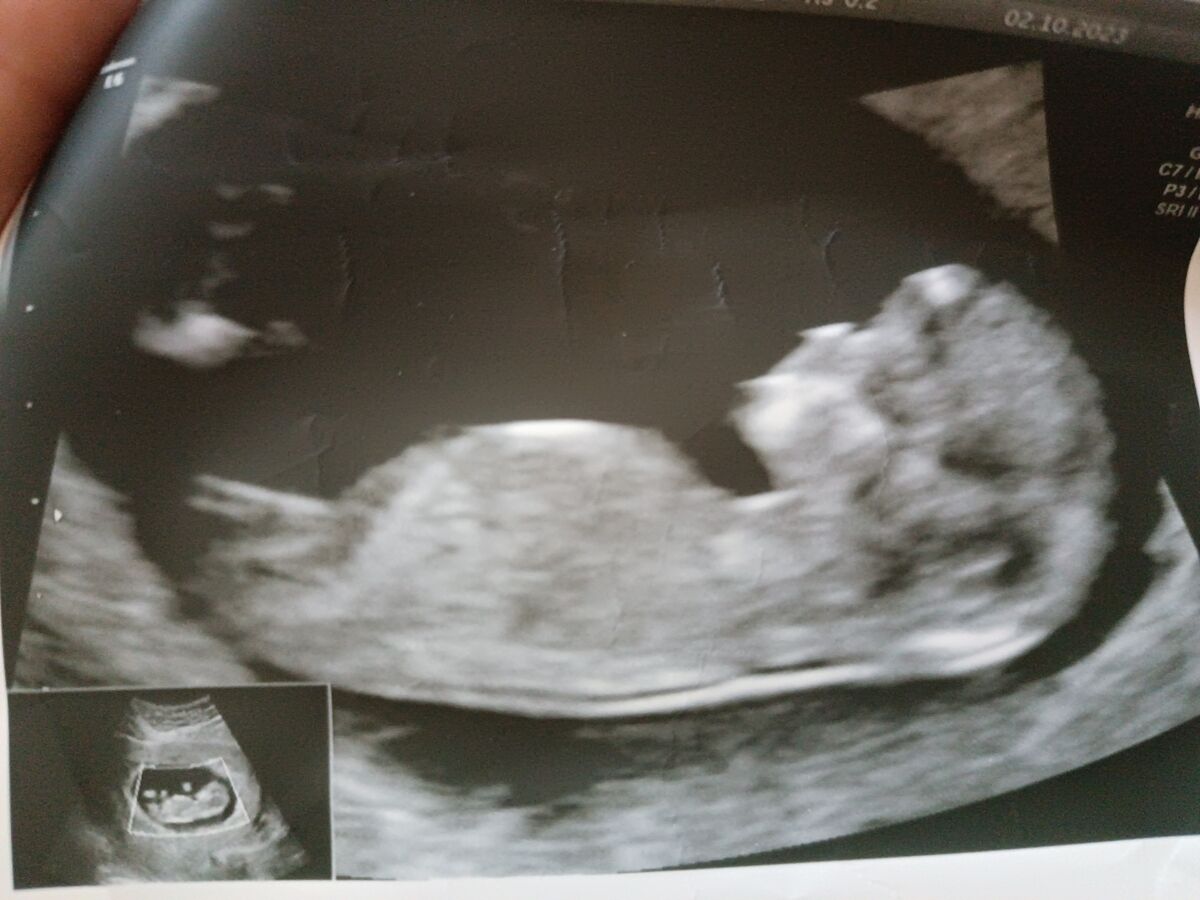

1 скринінг. УЗД 3-Д. Хлопчик чи дівчинка?)

Лікар сказав гадати рано , а от чоловік бачить яєчка ? А ви як думаєте: хто на фото?

Чоловік бачить, що хоче бачити. На такому терміні стать передбачають за непрямими ознаками , а не «о, я бачу яєчка»

Я читала що на такому терміні дивляться під яким кутом той бугорок і може сказати дуже досвідчений фахівець

Немає ще там видимості, то може бути і клітор дівчинки і чоловічі органи, треба ще почекати. Зараз 50/50))

На першому скринінгу не буде видно яєчок.Почитайте на якому терміні вони опускаються і їх буде видно.Мені здається яєчка опускаються після 16 тижня,а то і пізніше.Все,що може бути видно-пісюн

Більше схоже на дівчинку. Яєчок там точно нема чи ще нема, а на цьому фото можна роздивитись під яким кутом бугорок. Саме так роблять припущення на цьому сроці.